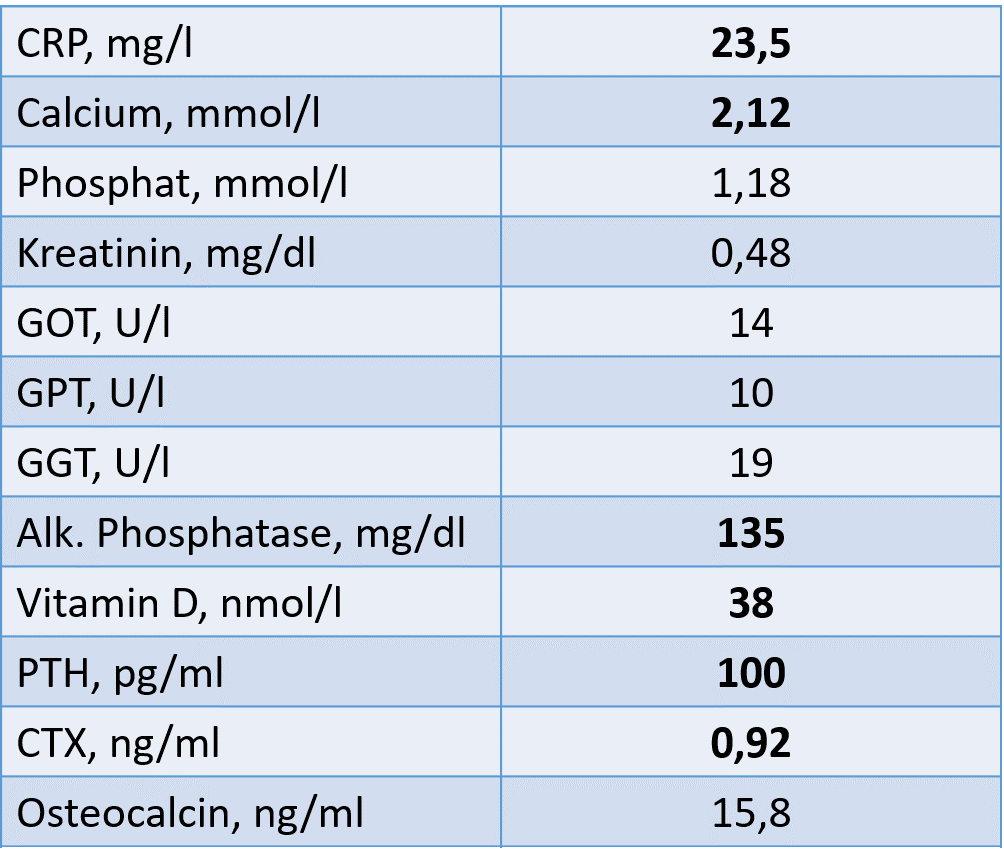

Labor:

Bei der Patientin liegt einerseits eine hochgradig reduzierte Knochenmineraldichte vor im Sinne einer sekundären manifesten Osteoporose mit multiplen atraumatischen Wirbelkörperfrakturen und andererseits zusätzlich eine

Osteomalazie. Die Ursache der Osteomalazie liegt in der Malabsorption, trotz hochdosierter Vitamin D Substitution liegt ein Mangel vor. Zudem wird zu wenig Calcium über den Gastrointestinaltrakt aufgenommen. Konsekutiv erhöht sich

das Parathormon um Calcium aus dem Knochen zu mobilisieren. Davon zu unterscheiden ist ein primärer Hyperparathyreoidismus, welcher zu einer Erhöhung des Serum-Calciumspiegels auf Basis einer autonomen Parathormonproduktion führt.

Ursächlich für die ausgeprägte Osteomalazie bei dieser Patientin ist ein schwerer Mangel an Vitamin D3 und Calcium. Ein Marker der Osteomalazie ist die Erhöhung der Alkalischen Phosphatase. Somit steht eine ausreichende Substitution

von Calcium und Vitamin D im Vordergrund der Behandlung. In diesem Fall hat die orale Substitution bisher keinen Erfolg gebracht, weshalb auch alternativ eine intramuskuläre Verabreichung sowie eine Umstellung der Galenik der oralen

Zufuhr sinnvoll ist. In diesem schweren Fall ist eine Kontrolle von Calcium, Phosphat, Alkalischer Phosphatase, Parathormon und Vitamin D3 alle 6-8 Wochen sinnvoll.

Eine antiresorptive Therapie ist kontraindiziert bei Patienten mit Osteomalazie. Eine spezifische Osteoporosetherapie darf erst nach Normalisierung von Calcium, Parathormon und Alkalischer Phosphatase eingeleitet werden.